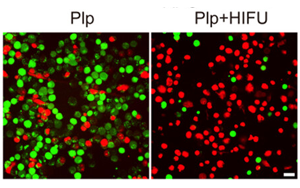

HIFU驅(qū)動靶向細胞焦亡治療基底樣乳腺癌:從基因篩選到血小板膜雜交脂質(zhì)體的協(xié)同機制探索

本文推薦了一種創(chuàng)新性治療策略:通過高強度聚焦超聲(HIFU)聯(lián)合生物信息學篩選與血小板膜雜交脂質(zhì)體(Plp)遞送系統(tǒng),實現(xiàn)基底樣乳腺癌(BLBC)的靶向細胞焦亡(pyroptosis)治療。